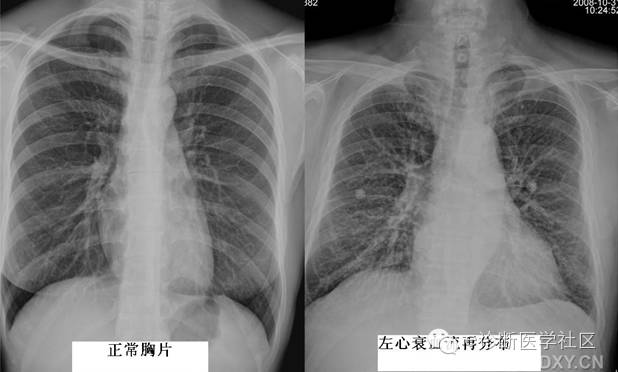

主要由肺充血和肺淤血引起肺充血多见于具有由左向右分流的先天性心脏病,如房间隔缺损、室间隔缺损等。这是由于肺血流量增加(动脉充血)使肺动脉扩张之故,表现为肺纹理较粗大,边缘较清楚,从肺门向肺内保持血管的特征。肺淤血多见于左心衰竭后肺静脉压力升高所致之肺静脉的扩张,表现为肺纹理增根、增多,边缘模糊,以两上肺野明显,肺野透过度减低。